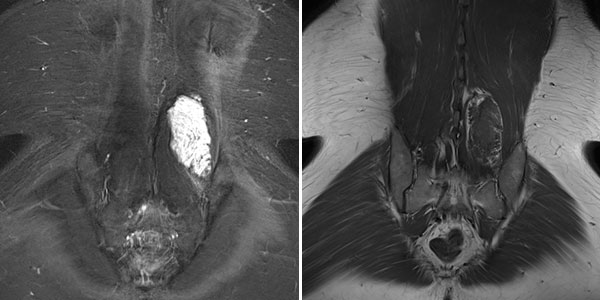

In der MRT in koronarer Schichtführung ist die Läsion sehr gut sichtbar. In der T2-gewichteten Sequenz mit Fettsättigung (linkes Bild) ist die Läsion stark hyperintens (weiß). In der nativen T1-Wichtung (rechtes Bild) praktisch isointens zur umgebenden Rückenmuskulatur. Beachte hier das randständig in der Läsion sichtbare, in T1-Wichtung hyperintense Fettgewebe.

In der axialen T2-gewichteten Sequenz der MRT liegt die Läsion in der autochtonen Rückenmuskulatur. Klassischer Flüssigkeits-Flüssigkeits-Spiegel durch schwerkraftbedingte Sedimentationseffekte bei dem in Rückenlage ruhig im Gerät liegenden Patienten.